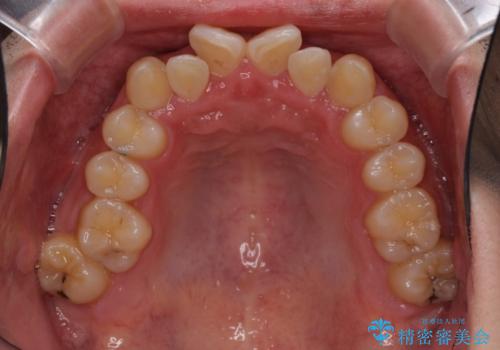

- 結婚式が近いとのことで、前歯のデコボコを改善したいと来院された患者様です。

口元の突出感はないものの、上顎前歯のデコボコが著しかったため、上顎左右第一小臼歯2本を抜歯することとしました。

咬合力が非常に強く、抜歯したスペースがなかなか閉じないであろうことは予想できましたが、思っていた以上に期間がかかりました。

前歯のすり減りも著しかったため、仕上げの位置の調整にも期間を要しました。